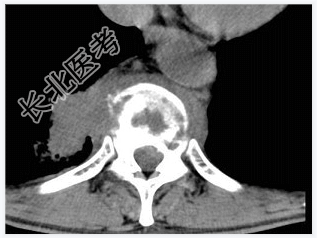

- [材料题] 男,32岁,低热、腰背痛,活动受限。

- 简答题1、结合CT检查,最可能的诊断是?